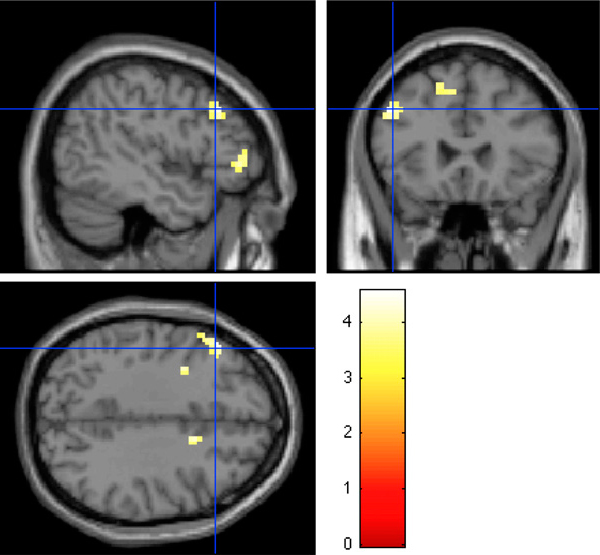

Сравнив активность мозга при удачном и неудачном запоминании картинок, авторы подтвердили то, что было известно и раньше: в формировании памяти участвуют многочисленные участки коры (лобной, теменной, височной, затылочной), а также кора островка, гиппокамп, миндалина и передняя поясная извилина (anterior cingulum). Выяснилось также, что в латеральной и медиальной префронтальной коре есть участки, которые при запоминании «негативных» картинок работают тем активнее, чем больше у человека А‑аллелей (то есть максимальная активность характерна для людей с генотипом АА, средняя — для АГ и минимальная — для ГГ). Это справедливо только для случаев успешного запоминания и только для «негативных» изображений. Для позитивных и нейтральных картинок никаких особых участков мозга, которые работали бы по-разному у людей с разными аллелями гена PRKCA, выявить не удалось.

Участки префронтальной коры, которые при успешном запоминании «негативных» изображений работают тем активнее, чем больше у человека копий аллеля А («гена хорошей памяти»). Изображение из обсуждаемой статьи в PNAS

Известно, что те участки латеральной и медиальной префронтальной коры, которые при успешном запоминании негативных картинок активнее работают у людей с аллелем А («геном хорошей памяти»), участвуют в формировании эмоционально окрашенных воспоминаний. Кроме того, недавно обнаружили, что повреждение медиальной префронтальной коры снижает риск развития ПТСР у ветеранов войн (M. Koenigs et al., 2008. Focal brain damage protects against post-traumatic stress disorder in combat veterans).